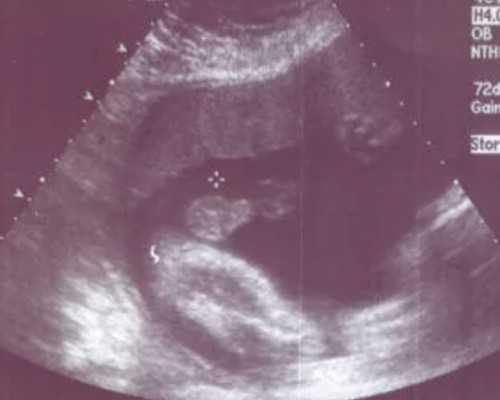

对于基础卵泡少的患者,一般在黄体中期开始用药,使体内促性腺激素处于低水平,用药8天左右月经来潮。月经第3-7天,开始肌肉注射促卵泡发育的药物;3天后B超监测卵泡发育情况,调节用药剂量;促卵泡发育药物应用10天左右,卵泡发育成熟;这时,经B超引导下,经阴道穹窿穿刺可取出卵子,在体外授精和进行第三代试管婴儿胚胎植入前遗传学筛查诊断。